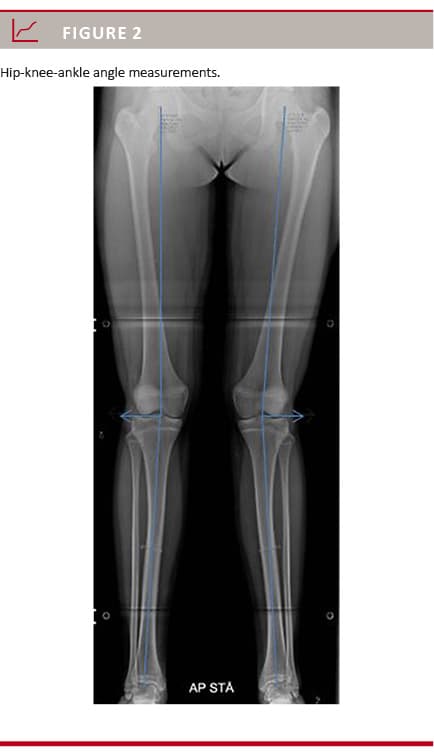

The HKA angle is the angle between the mechanical axis of the femur and the tibia [4, 6]. It is obtained by connecting the centre of the femoral head to the midpoint of the tibial eminential spine in a line tangential to the femoral condyles, and another line from here to the centre of the trochlea tali (Figure 2)

. The HKA angle can also be expressed as x degrees of deviation from a neutrally aligned lower extremity (180°) [9]. We measured the length of the tibia and the femur along the anatomical axis. The radiographs were primarily obtained in a standardised fashion, and all HKA angles, tibia and femur lengths, were measured using Impax 6.3.1 (AGFA HealthCare, Denmark). All measurements were made by the same radiologist (MBH). For data analysis, the right and the left HKA angles were added to allow data to be correlated with the measured IM distances.